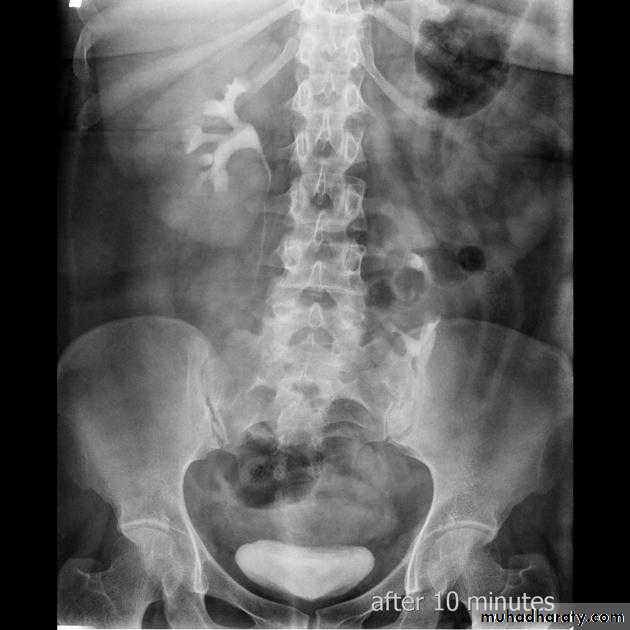

IVU shows :

Marked dilatation of pelvis and may be extra-renal.

Calyceal dilatation is late and in advanced cases form foot shape PCS

The ureter is not seen and when it is seen looksnormal .

Delayed film with I.V. diuretic produce gross dilatation .